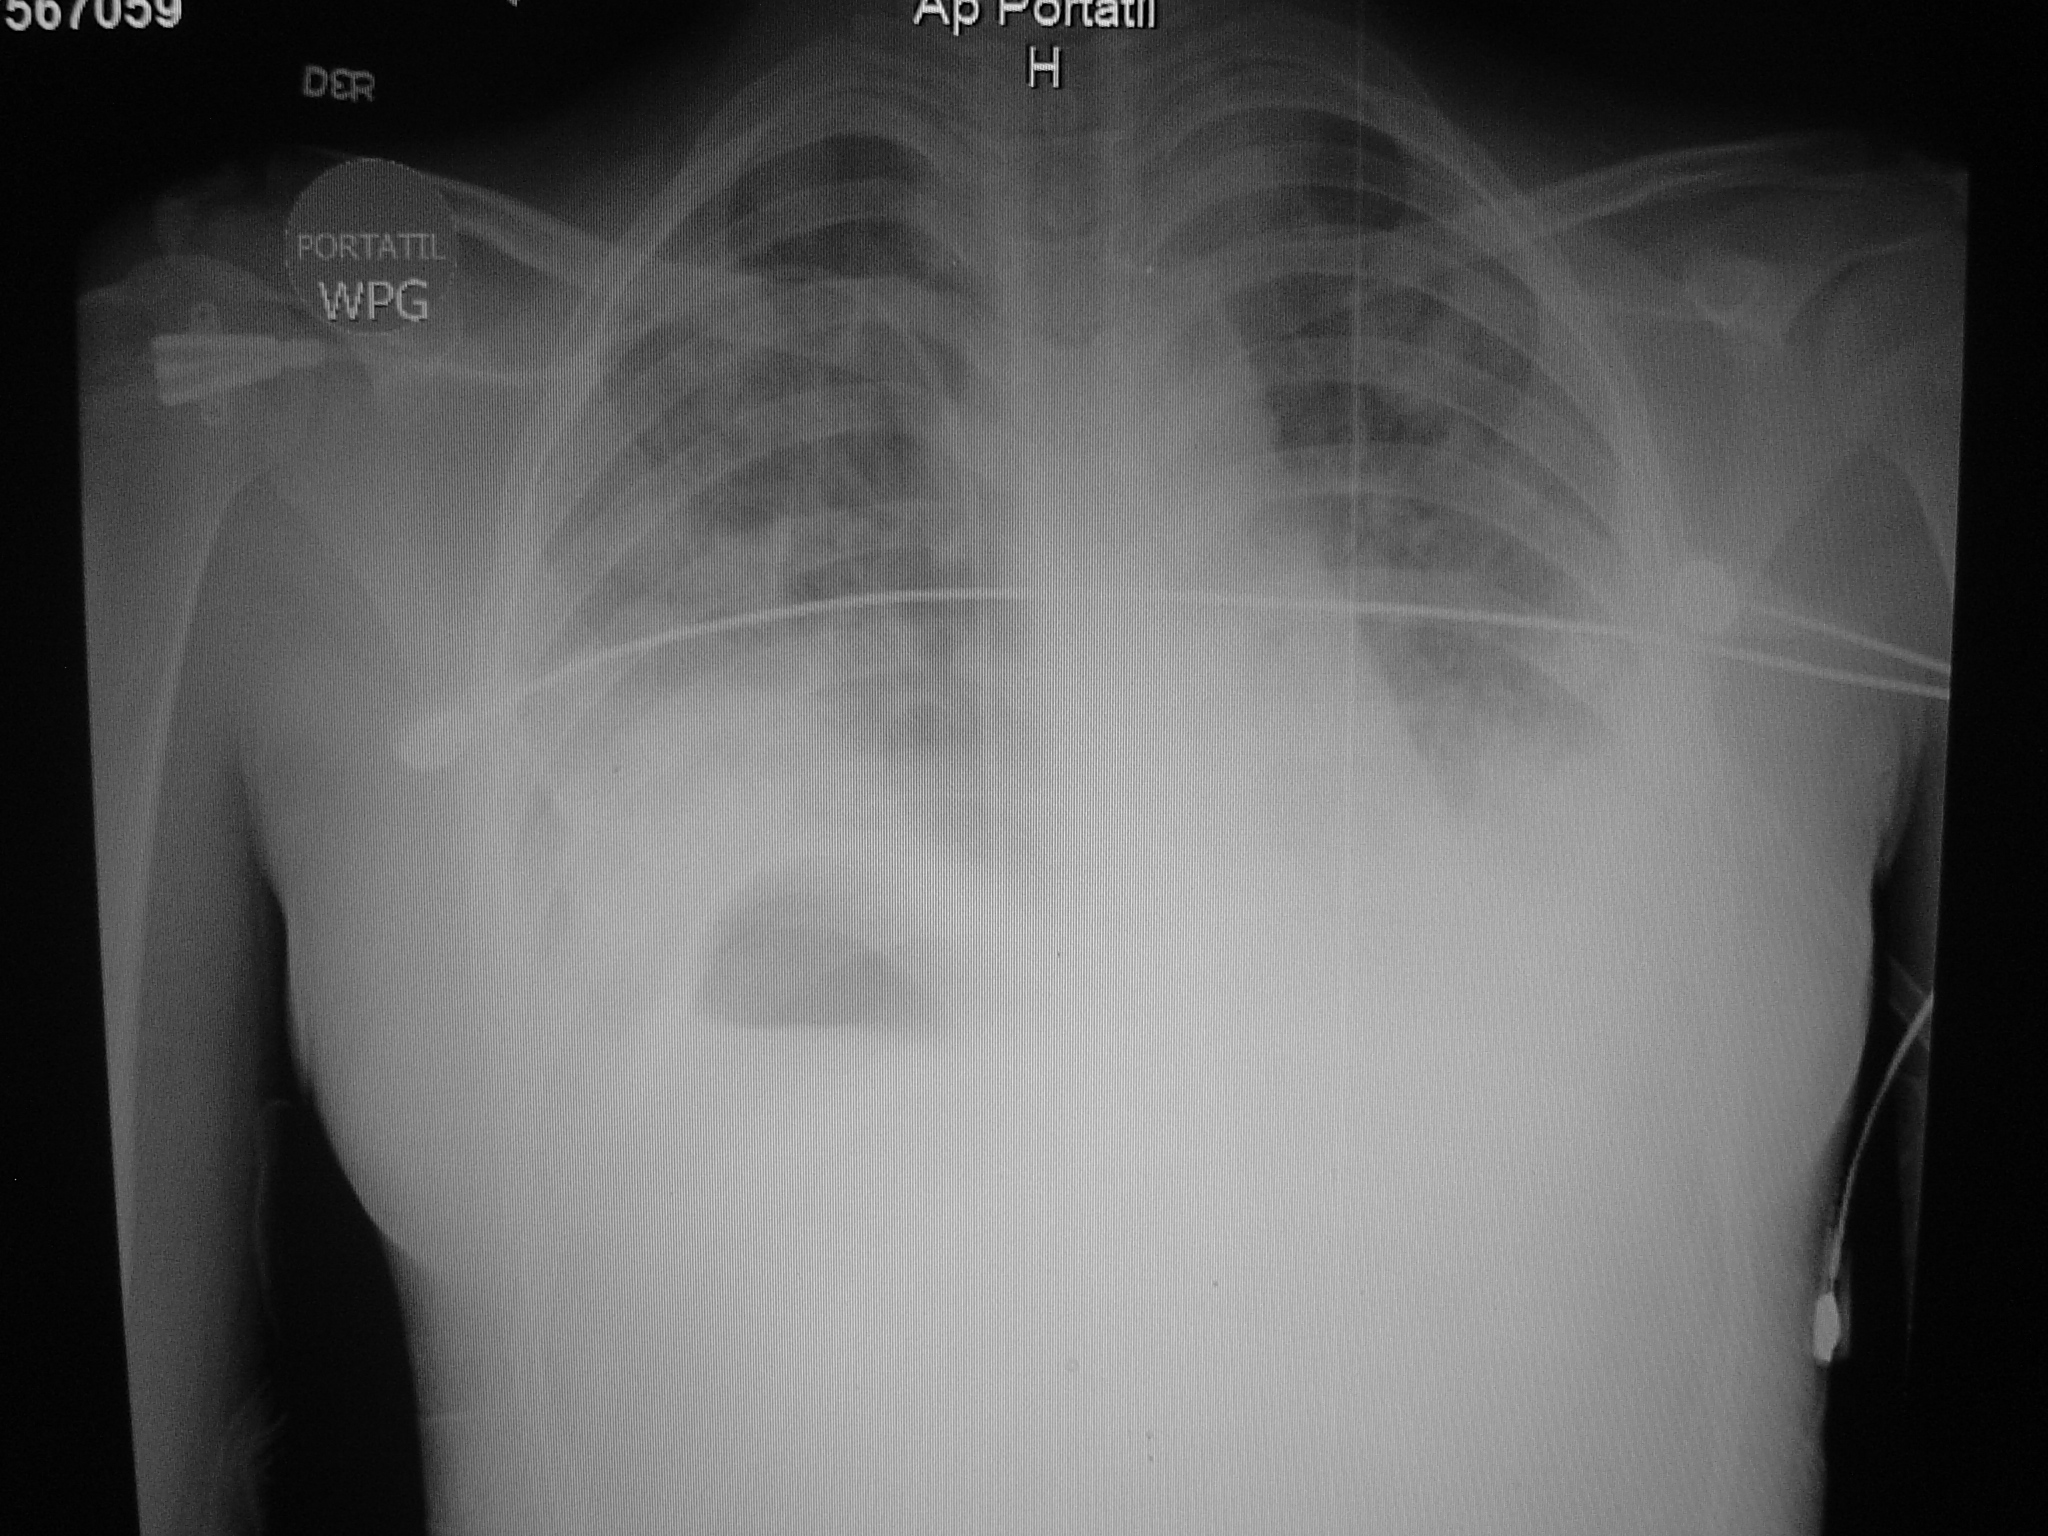

El amplio espectro clínico de la neumonía adquirida en comunidad genera problemas para su diagnóstico. La neumonía producida por Staphylococcus aureus es conocida como necrotizante, de rápida evolución y alta mortalidad. Se describe el caso de una mujer de 14 años con neumonía necrotizante por S. aureus resistente, evolucionó rápidamente a insuficiencia respiratoria requirió ventilación mecánica presento bacteriemia, empiema, neumatoceles, neumotórax bilateral persistente con fistulas broncopleurales que requirieron corrección quirúrgica. No se detectaron factores de riesgo. Los cultivos en sangre, líquido pleural, lavado traqueal fueron positivos y el tratamiento fue exitoso.